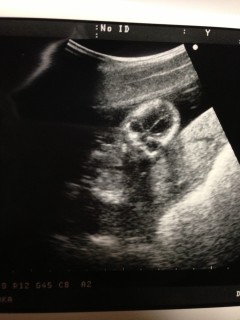

こんばんは。今日で五ヶ月になり診察にいきました。エコー写真を撮って頂いていると始めはうつ伏せになっていましたが3秒間程横向きになった時に、股あたりに白い丸い物が二つ見えました。男の子なのかな?わかる方いらっしゃいませんか?

こっちを向いている写真です(^_^)